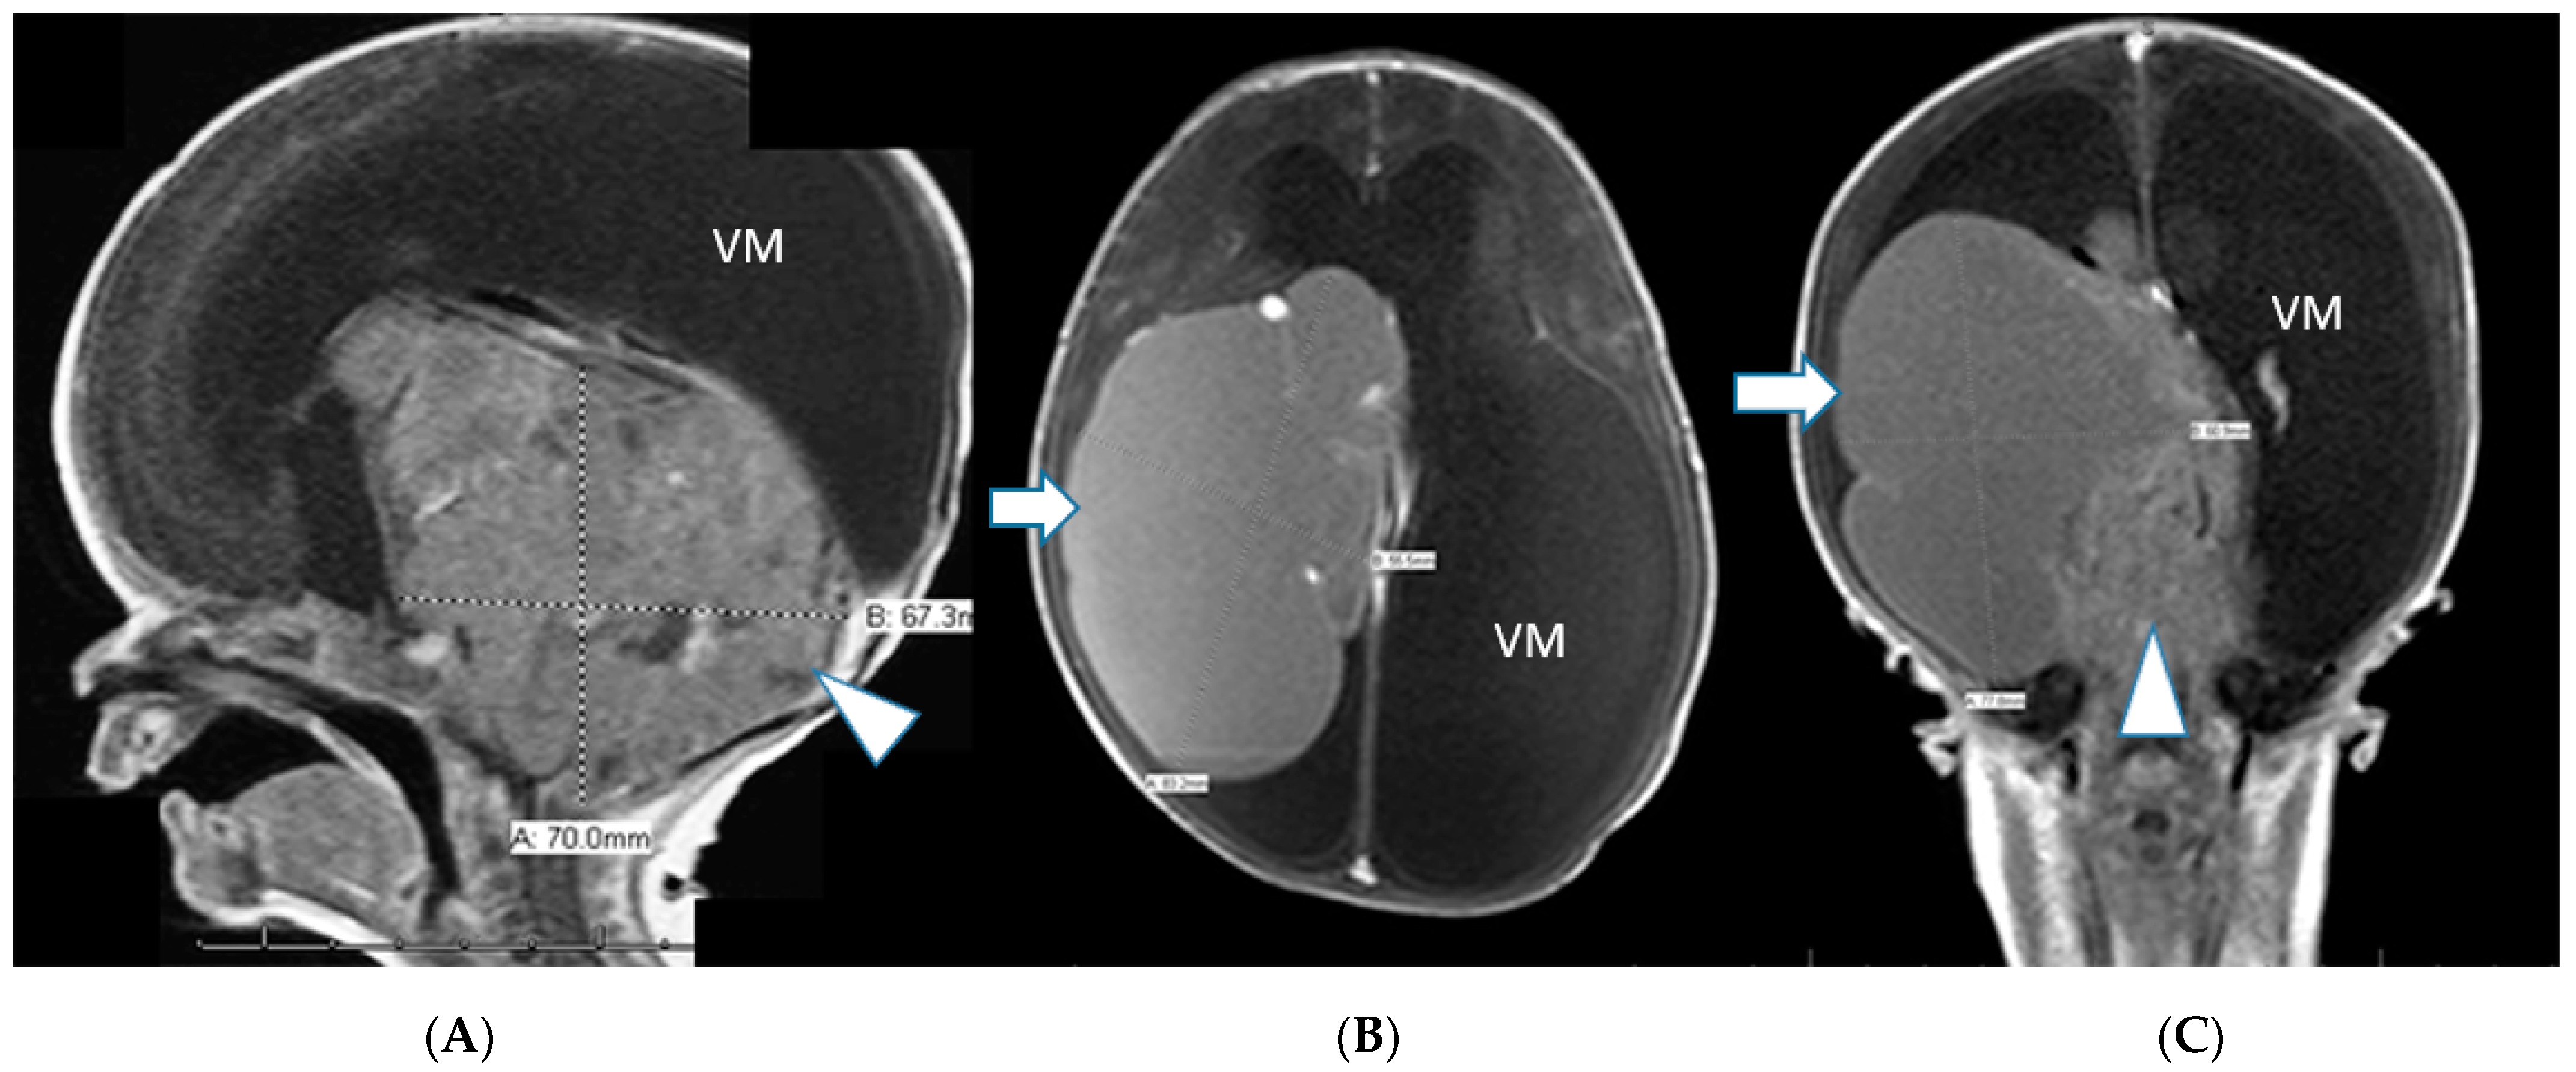

2. Case Series